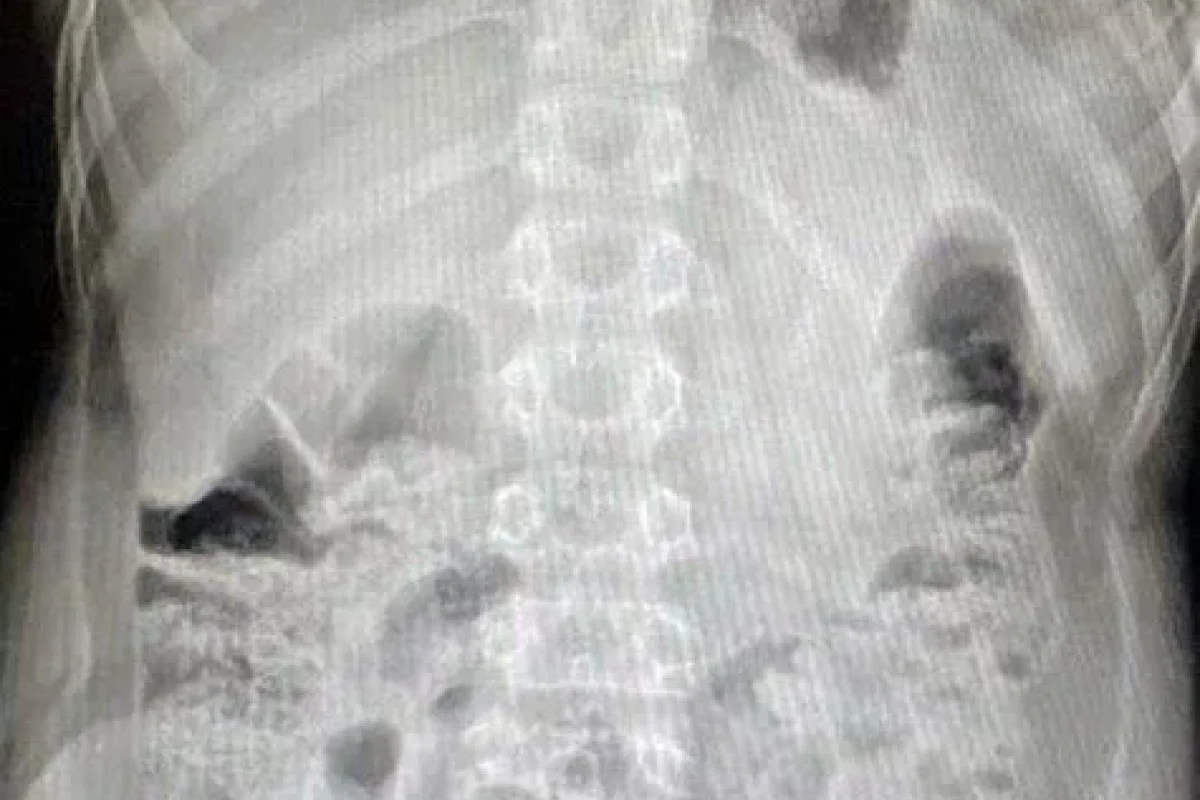

Moskvada G.N. Speranski adına Uşaq Xəstəxanasının həkimləri təsadüfən televizorun pultundakı barmaq tipli batareyanı udan 12 yaşlı oğlan uşağını xilas ediblər.

Valideynləri uşağı dərhal xəstəxanaya gətiriblər və onun televizor pultundakı batareyanı udduğunu bildiriblər. Yad cisim kor bağırsağa qədər düşüb.

Həkimin sözlərinə görə, batareya hələ oksidləşməyə başlamayıb, bu səbəbdən kimyəvi yanıq baş verməyib. Uşaq iki gün sonra tamamilə sağlam şəkildə evə buraxılıb.